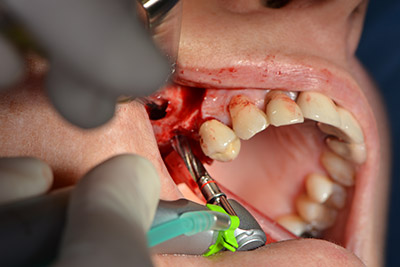

The following holes were drilled at a reduced speed of 300 rpm. The Implantmed demonstrated its true capability at this stage. The surgical protocol can be preset – the various positions can be selected simply by pressing the “P” position of the foot control (Fig. 10 to 11).

The next programmed position is the placement of the implant and in our practice it is preset to a force of 32 Ncm (Fig. 12).